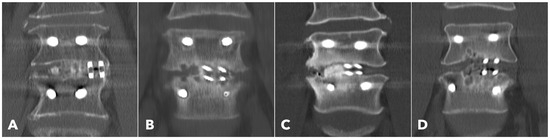

Lumbar spine computed tomography (CT) with 3 mm thin-slice coronal and sagittal reconstructions was performed one year after the surgery. Fusion status was assessed using the Bridwell grading system based on bone window images (Figure 4). Grades I and II were defined as successful fusion. Cage subsidence was defined as sinking > 2 mm beyond the bony endplate [24,30]. The presence of subchondral osteolysis was also recorded as a potential indicator of pseudoarthrosis (Figure 5).

Figure 4. Postoperative 1-year CT reconstruction to evaluate the Bridwell fusion grade. (A) Grade I solid fusion with remodeling of the trabeculae. (B) Grade II fusion with bridging bone formation and no radiolucency between the cages and the endplates. (C) Grade III fusion with radiolucency between the bone graft and endplate. (D) Grade IV fusion with resorption of the bone graft.